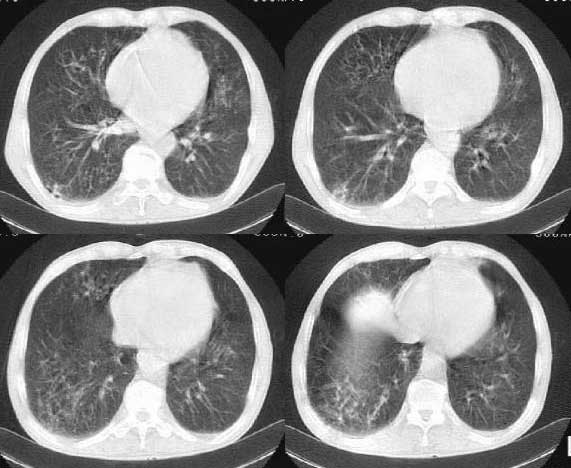

以下是引用woaixct在2006-6-23 12:15:00的发言:[br]第一张胸片示:右肺上叶为大片致密影占据,左肺上见大片致影及空洞性病灶并有液平;[br]第二张胸片示:左肺上叶致密影及空洞性病灶基本吸收,而右肺上叶之病灶有少许吸收改变;[br]ct片示:右上叶大片软组织密度,右肺门区至右肺上叶见巨大软组织块,内见支气管充气征,上纵隔右移,主气管及上叶支气受压变扁,中间支气管狭窄,左肺上叶空洞性病灶并有液平,左肺上叶尖后段见大片致密影,结合2张胸片考虑,ct片是4月份所摄,而不是6月份的片子;[br]结合2张胸片及ct片考虑:[br] 1.右中央型肺癌伴右肺上叶不张;[br] 2.左肺上叶尖后段炎性变及左肺脓肿;[br]第2张胸片提示:经过一个多月的不规则抗炎治疗,左肺上叶病灶及右肺上叶不张病灶基本吸收,而右肺占位无明显变化。

以下是引用jiangjing在2006-6-23 21:21:00的发言:[br]个人考虑还是两肺感染性病变可能大,主支气管及叶支气管是通畅的,并可见支气管气相;ct提示病变是以肺叶分布的,密度相对均匀;胸片可见有叶间裂下坠征,是不是考虑克雷伯杆菌感染可能.病人前后两张片比较病变是增多[应该考虑混合感染可能性大,右肺癌待排建议查痰及穿刺检查]